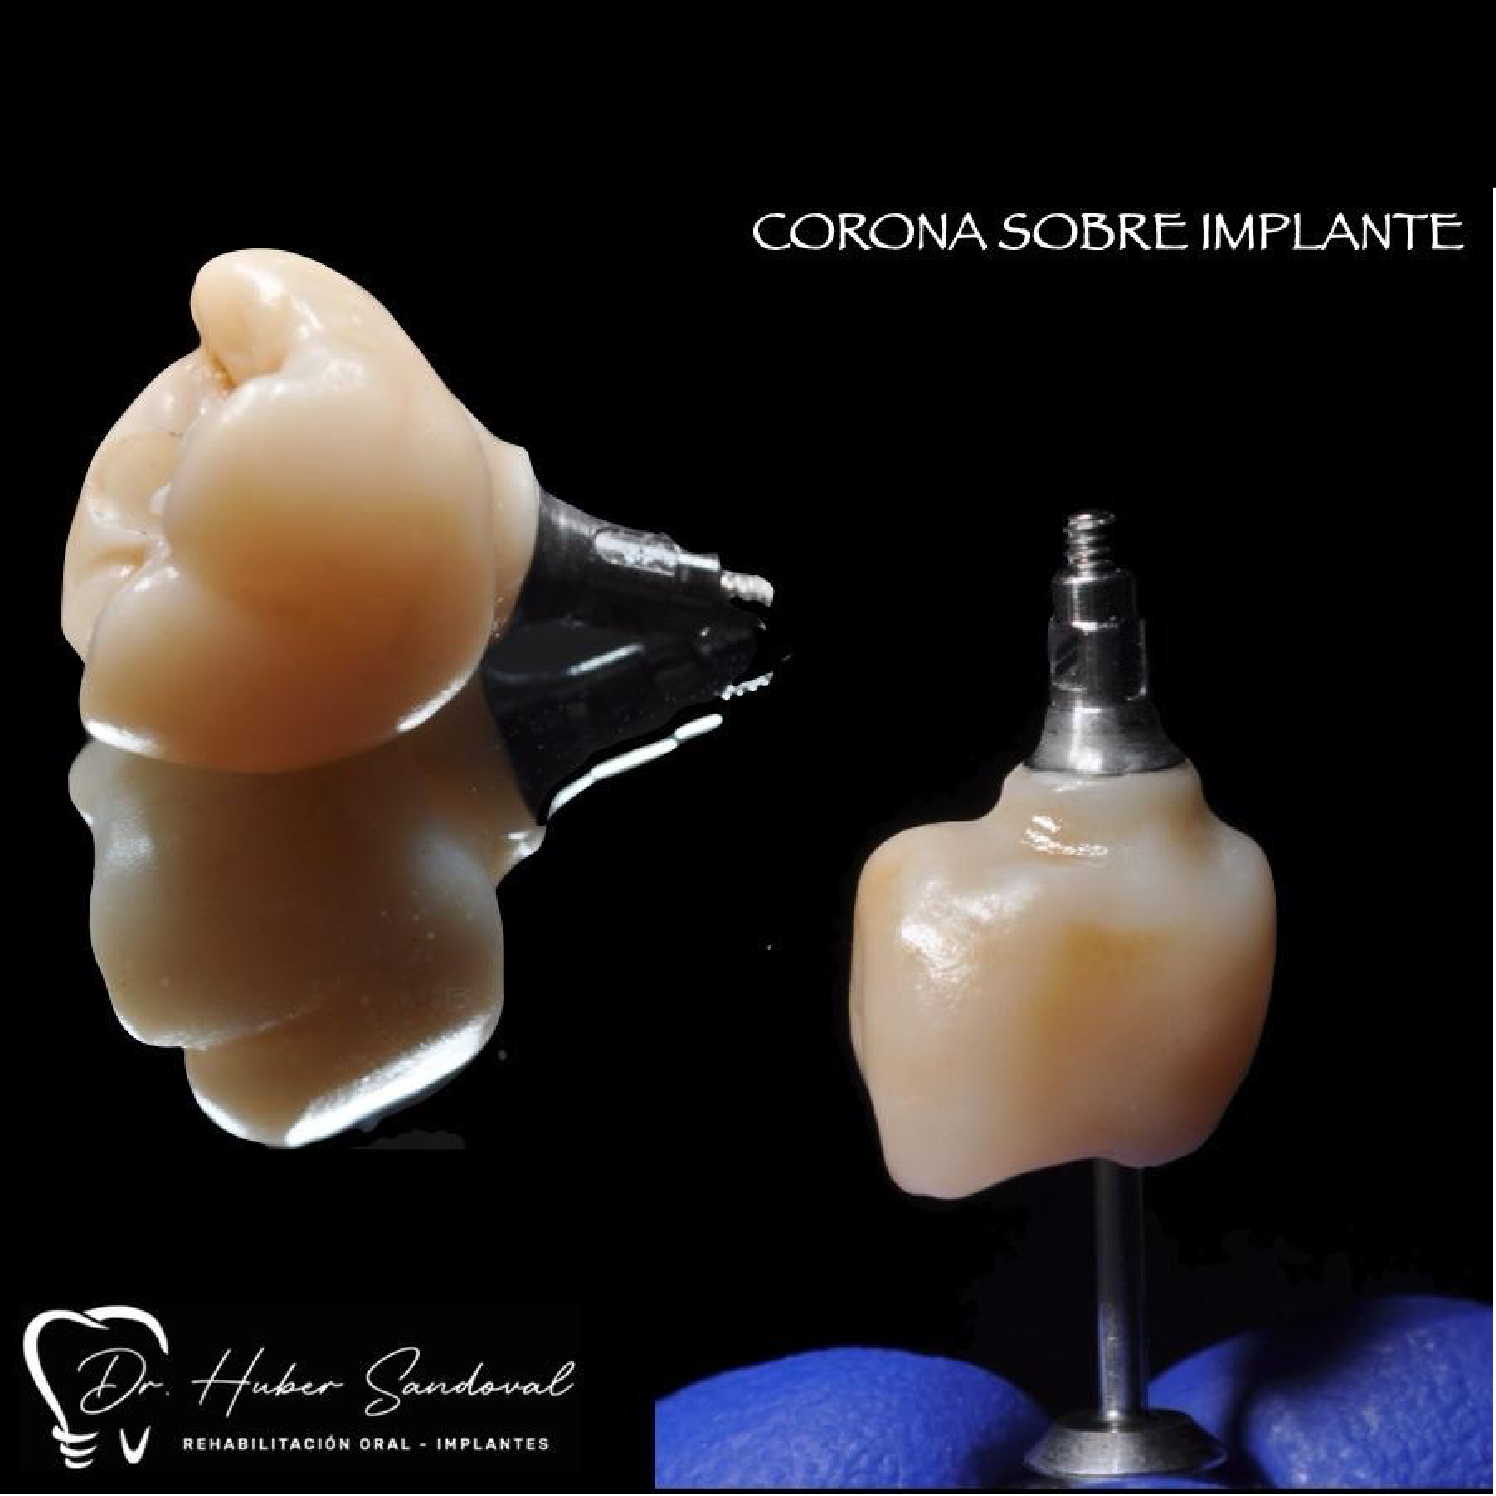

- Colocación de la corona: se fija la prótesis definitiva que luce como un diente natural.